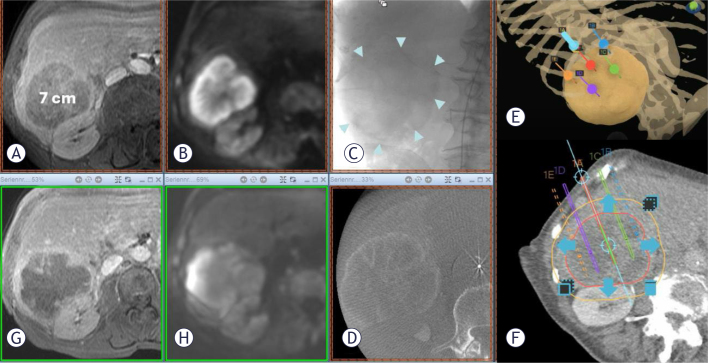

Background: Electrochemotherapy (ECT) is a local nonsurgical effective tumor treatment in the hand of the clinician for the treatment of patients with liver tumors or metastases. The study aimed to test the technical feasibility and safety of intra-arterial (i.a.) bleomycin administration compared to the established intravenous (i.v.) administration in percutaneous electrochemotherapy (pECT). Furthermore, the equivalence hypothesis was tested between the 2 modalities in terms of local short-term response and progression-free survival.

Patients and methods: Forty-four patients have been recruited and treated by pECT for hepatocellular carcinoma, cholangiocarcinoma and liver metastatic lesions from cancers of different origin: 18 were treated with standard i.v., 26 with bleomycin i.a. administration.

Results: The 2 groups were similar for anagraphic and anamnestic data, as well as for most relevant disease specific characteristics. Technical success of the treatment was obtained in 95% and 100% of patients in i.v. and i.a. groups respectively. Short-term local response was similar in the 2 groups with a slightly higher complete remission (CR) rate in the i.a. group. There were 61.9% CR, 23.8% partial remission (PR), 4.8% stable disease (SD) in the i.v. group, and 80.6%, CR 12.9% PR, 3.2% PD (p = 0.3454). One-year progression free survival was 60% (C.I. 33%-88%) in the i.v. group and 67% (C.I. 42%-91%) in the i.a. group (p = 0.5849).

Conclusions: The results of this study confirmed the safety and feasibility of super-selective i.a. bleomycin administration. Analysis of local response and progression free survival confirmed the equivalence hypothesis of the new modality compared to standard i.v. administration in the treatment of primary and secondary liver malignancies by pECT.